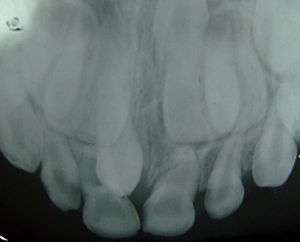

| Supernumerary teeth in the premaxillary area | |

Hyperdontia is the condition of having supernumerary teeth, or teeth that appear in addition to the regular number of teeth. They can appear in any area of the dental arch and can affect any dental organ.

There is evidence of hereditary factors along with some evidence of environmental factors leading to this condition. While a single excess tooth is relatively common, multiple hyperdontia is rare in people with no other associated diseases or syndromes.[3] Many supernumerary teeth never erupt, but they may delay eruption of nearby teeth or cause other dental or orthodontic problems.[4][5] Molar-type extra teeth are the rarest form. Dental X-rays are often used to diagnose hyperdontia.